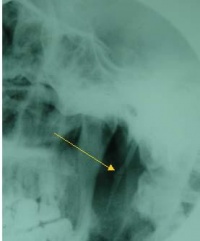

查体:触诊扁桃体区可扪到坚硬条索状或刺状突起,患者可诉此处为不适之处,并可诱致咽痛或咽痛加重。多为单侧过长。茎突X线片常显示其长度过长,或有偏斜、弯曲等情况。